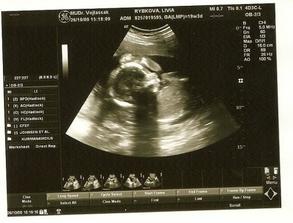

Po roku dlhého skúšania sa nám konečne podarilo...Sme s manželom veľmi šťastní a nevieme sa našeho prvo-rodeného bábatka dočkať.

Takže držím aj vám palčeky lebo to je naozaj nádherný pocit že budete matkou a nosíte to malé pod srdcom sa nedá opísať.